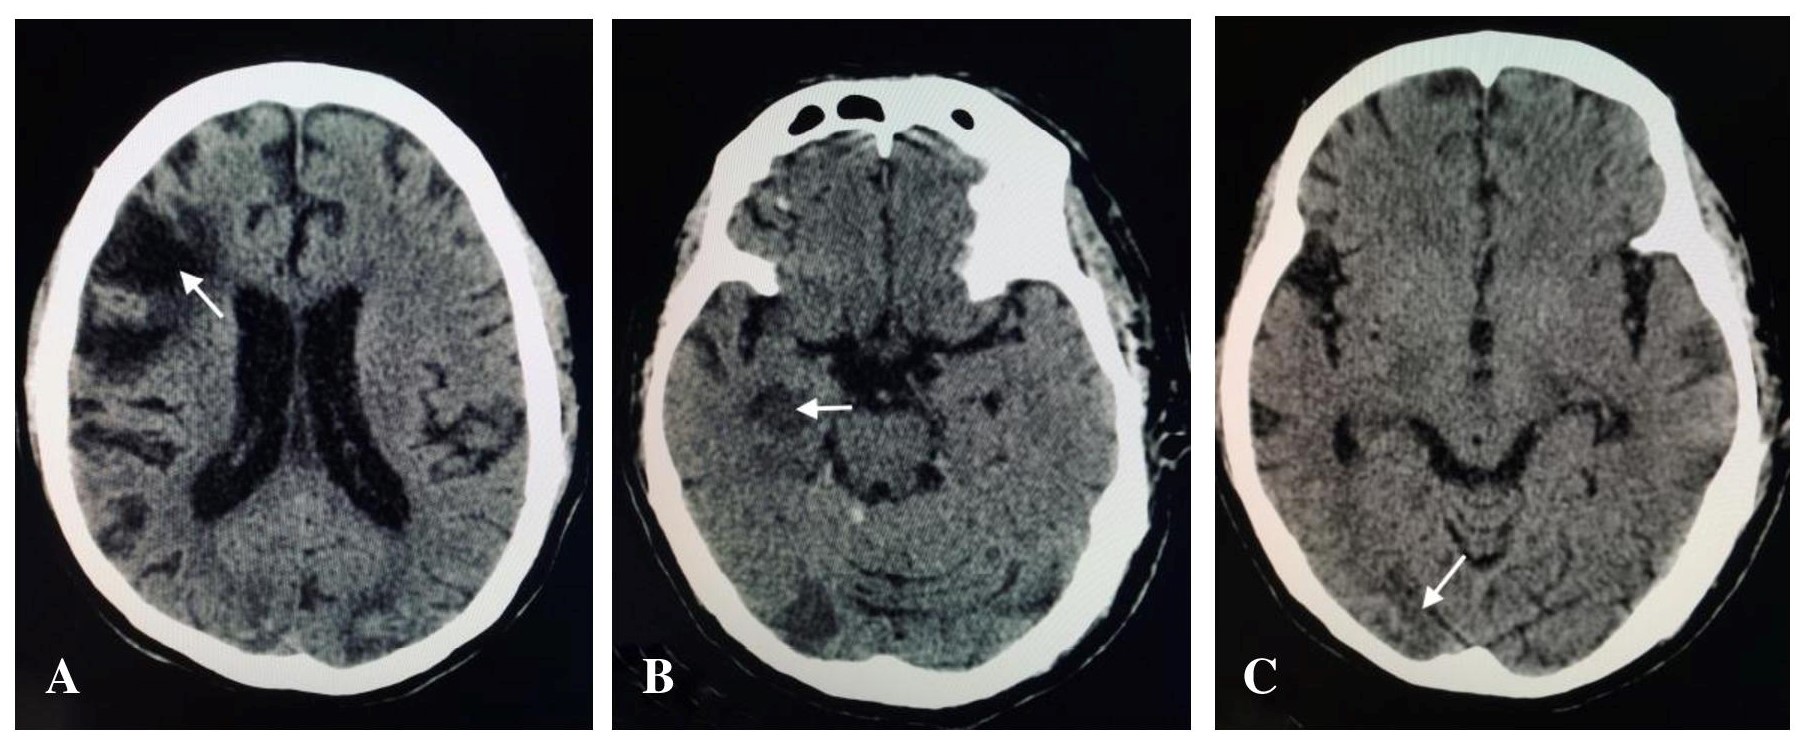

The patient is a 64-year-old male who presented with right-sided body weakness but without episodes of chest pain, dyspnea, orthopnea or palpitations. Consultation was done and he was advised surgical intervention, hence admitted in our institution. During his hospital stay, computed tomography (CT) scan of the head was done revealing finding of acute infarct in the right thalamus and right hippocampus, and old hemorrhagic infarct in the right frontal lobe and bilateral occipital lobes (Figure 1).

Figure 1. A. CT scan of the head showing encephalomalacic changes in the right frontal lobe. B. Acute infarct involving the right hippocampus. C. Hemorrhagic infarct in the occipital lobe.

The clinical presentation involved in cardiac tumors is usually divided into cardiac symptoms (dyspnea, palpitations, angina, arrhythmias, and cyanosis), systemic manifestations (fever, cachexia, arthralgia, Raynaud’s phenomenon, rash, and anemia), and embolic manifestations.[14] Our patient suffered from two episodes of stroke a year apart. On CT, acute infarct involving the right thalamus, and right hippocampus is seen. Old hemorrhagic infarcts involve the left frontal lobe and bilateral occipital lobes. According to Dias et al, primary cardiac tumors should be considered as a possible cause for embolic manifestations. In his study, cardiac myxoma was the most common cause at 72.6%, followed by fibromas at 6.9%, thrombi at 6.4%, and lastly sarcomas at 6.4%.[14] Surgical resection of cardiac tumors remains the treatment of choice in symptomatic cases.[15] Metastasis is rare but tumor recurrence has been reported.[11]